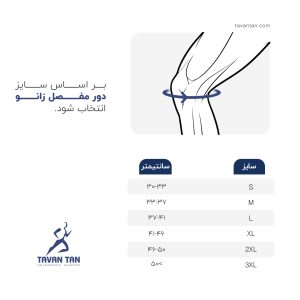

| سایز | S, M, L, XL, 2XL |

| رنگ | کرم, مشکی |

انتخاب زانوبند طبی باید بر اساس نوع آسیب، سطح فعالیت و سایز دقیق زانو انجام شود. زانوبندها در مدلهای مختلفی مانند کشی، بنددار، فنردار یا دارای پد سیلیکونی عرضه میشوند که هر یک کاربرد خاص خود را دارند. مشورت با پزشک یا فیزیوتراپیست پیش از خرید زانوبند توصیه میشود تا مناسبترین مدل انتخاب شود.

کد محصول:KN002| سایز | S, M, L, XL, 2XL |

| رنگ | کرم, مشکی |